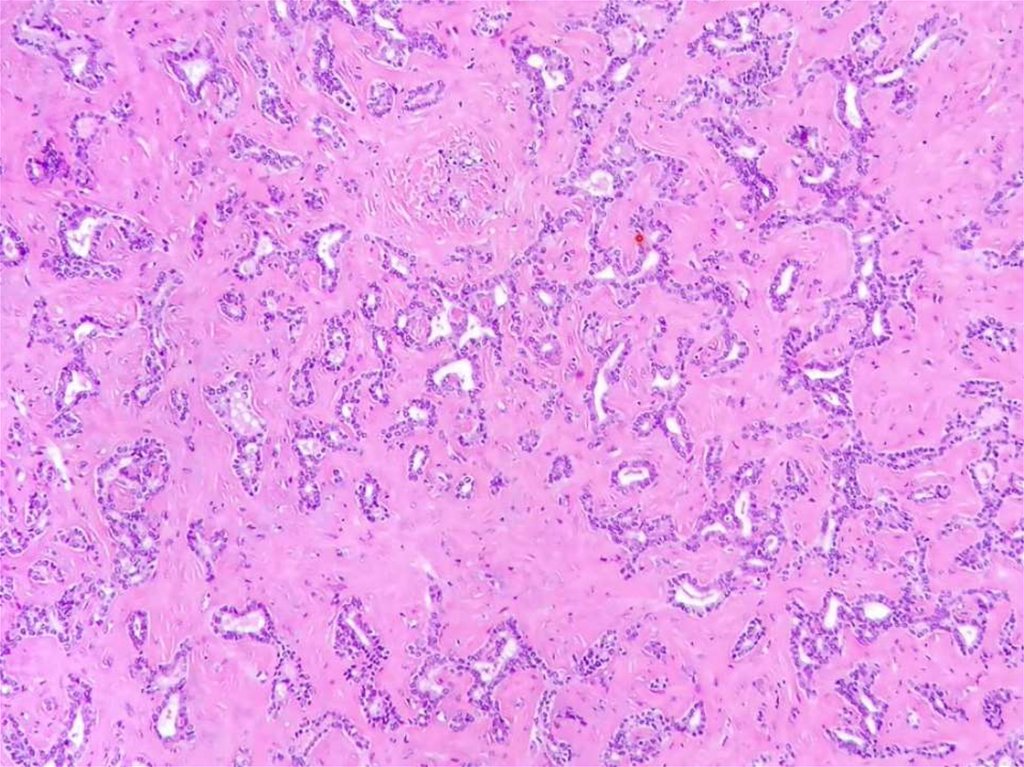

Cholangicarcinoma